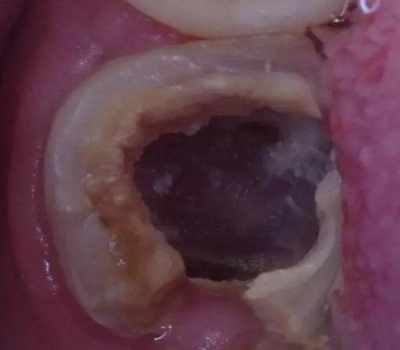

因為腐質(zhì)比較多用剔挖器處理:

剔挖器進(jìn)一步處理后見到底穿部位:根管挖匙派上用場,穿孔部位有少許膿液。